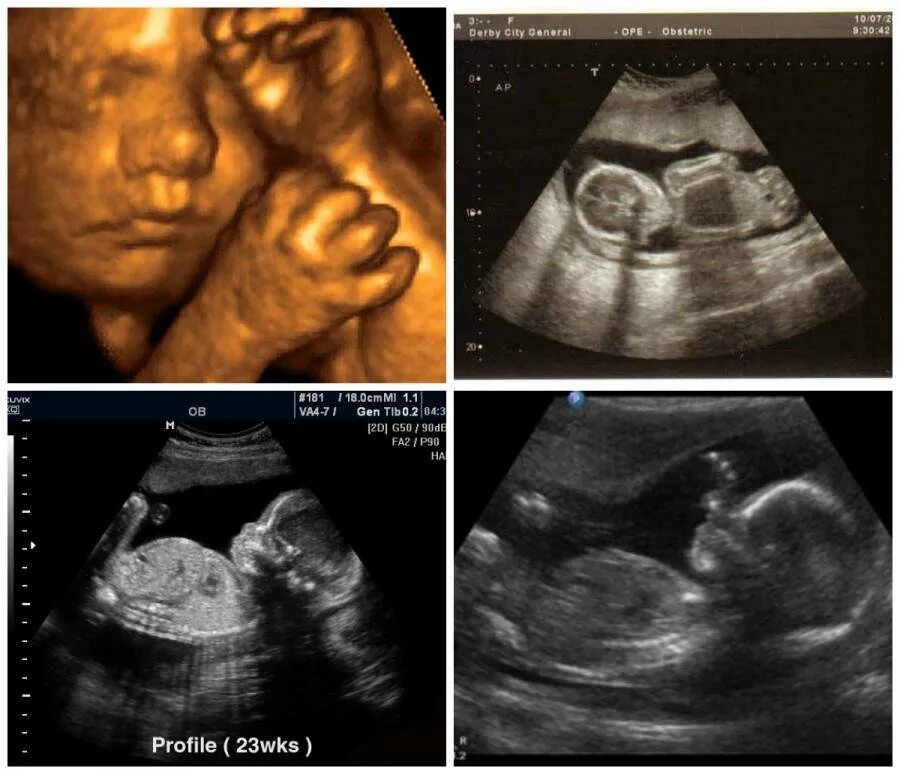

Развития плода 30 недель